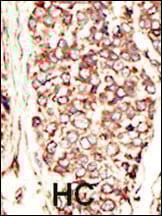

IHC (Immunohistochemistry)

(Formalin-fixed and paraffin-embedded human breast carcinoma tissue reacted with HER2/ErbB2 antibody (N-term) , which was peroxidase-conjugated to the secondary antibody, followed by DAB staining. This data demonstrates the use of this antibody for immunohistochemistry; clinical relevance has not been evaluated.)

IHC (Immunohistochemisry)

(Formalin-fixed and paraffin-embedded human cancer tissue reacted with the primary antibody, which was peroxidase-conjugated to the secondary antibody, followed by AEC staining. This data demonstrates the use of this antibody for immunohistochemistry; clinical relevance has not been evaluated. BC = breast carcinoma; HC = hepatocarcinoma.)